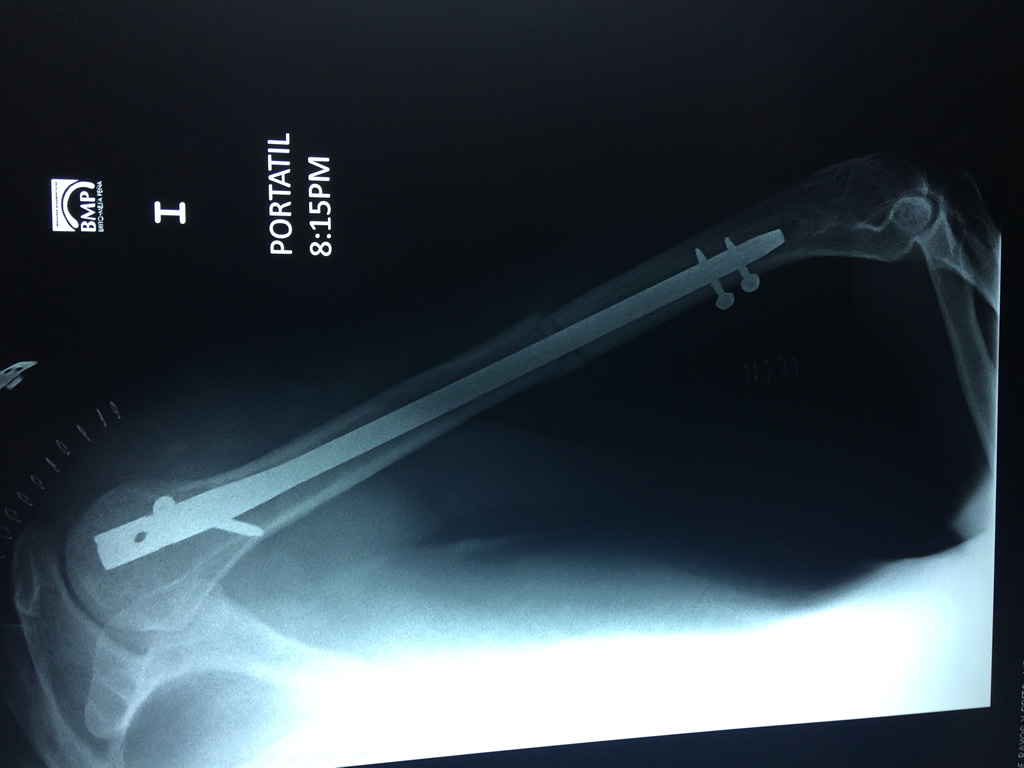

Cirugías de Peroné y Tibia

El Húmero (en latín, humerus) es el hueso más largo de las extremidades superiores en el ser humano. Forma parte del esqueleto apendicular superior y está ubicado en la región del brazo. ... El extremo proximal del húmero tiene la cabeza, cuellos quirúrgico y anatómico y tubérculos mayor y menor.